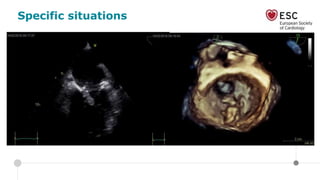

Specific situations

• 69 year old female

• Hypertension, diabetes

• Chronic atrial fibrillation

• Admitted with neurologic symptoms: disoriented, confused,

inappropriate reactions to normal requests since 2 days

• HR 89 bpm, BP 130/70 mmHg, T 39°C

• Systolic murmur

• Blood test: CRP 346, Leucocytosis, Hb 7.6, INR 2.5,

Thrombocytes 478, Na 142, K 3.7, eGFR 78